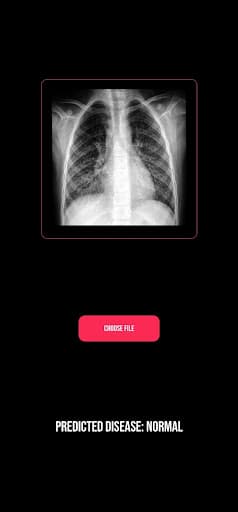

ProjectK is an AI-powered app that can detect pulmonary diseases by analyzing lung X-rays. I made it during a hackathon.

Screenshot 1 of ProjectKScreenshot 2 of ProjectKScreenshot 3 of ProjectKScreenshot 4 of ProjectKScreenshot 5 of ProjectKScreenshot 6 of ProjectK